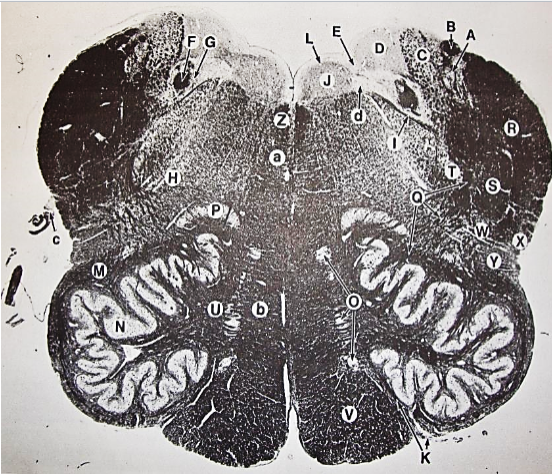

A

fasciculus gracilis

B

gracile nucleus

C

fasciculus cuneatus

D

cuneate nucleus

F

internal arcuate fibers

G

decussation of internal arcuate fibers

H

medial lemniscus

I

hypoglossal nucleus

J

dorsal motor nucleus vagus

K

solitary fasciculus

L

solitary nucleus

M

dorsal longitudinal fasciculus

N

spinal trigeminal tract

O

spinal trigeminal nucleus

P

posterior spinocerebellar tract

Q

anterior spinocerebellar tract

R

spinal lemniscus

S

lateral vestibulospinal tract

T

rubrospinal tract

U

lateral reticular nucleus

V

medial accessary olivary nucleus

W

pyramidal (corticospinal) tract

X

arcuate nucelus

Y

medial longitudinal fasciculus

Z

tectospinal tract

a

fascicles of hypoglossal nerve